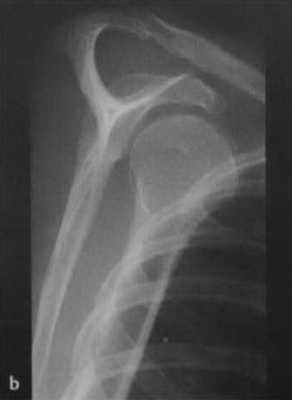

Задний вывих: головка плечевой кости перекрывает границу суставной полости; суставная щель не визуализируется.

а, b Задний вывих плечевого сустава у женщины 45 лет после падения с велосипеда, (а) Рентгенологическое исследование правого плечевого сустава. Суставная щель в прямой проекции не визуализируется, плечо ротировано медиально.(b) Y-проекция четко демонстрирует задний вывих.